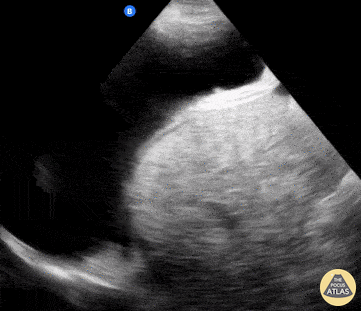

A 54-year-old male with hx chronic, untreated HCV complicated by cirrhosis presented with subacute dyspnea and abdominal distention. POCUS was notable for both a pleural effusion (anechoic fluid with atelectatic lung floating within it) as well as ascites (anechoic fluid underneath the mobile diaphragm). This history and POCUS findings were consistent with his diagnosis of hepatic hydrothorax. Shahad Al Chalaby, MD. PGY-2, Internal Medicine Highland Hospital. Alameda Health System Internal Medicine Residency Program. CA, USA @shahad_Chalaby